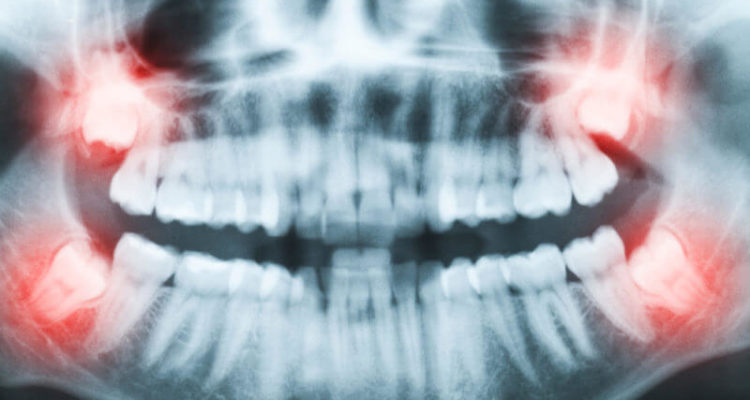

У деяких випадках лікарі рекомендують відразу позбутися від “вісімок”. По-перше, до стоматолога потрібно звернутися при недостатньому прорізуванні, болі і набряку щелепної кістки або ясен, ризик розвитку карієсу.

По-друге, видалення рекомендується при неправильному розташуванні зубів, наприклад, коренем в бік. Через тиск на сусідні зуби відбудеться зміщення всього ряду. У серйозних випадках може знадобитися операція. На відновлення після видалення зазвичай йде близько двох тижнів. На цей період медик може призначити болезаспокійливі і протизапальні препарати.